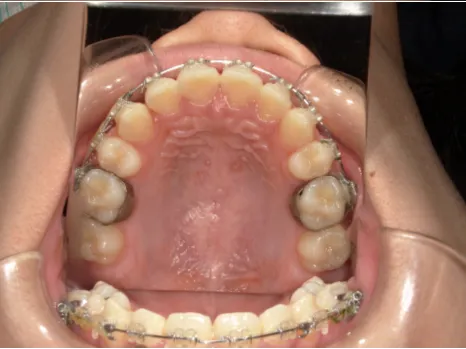

治療後⑩高2:17y7m 抜歯治療終了

口元の治療前後:15y5m→17y7m スッキリしました